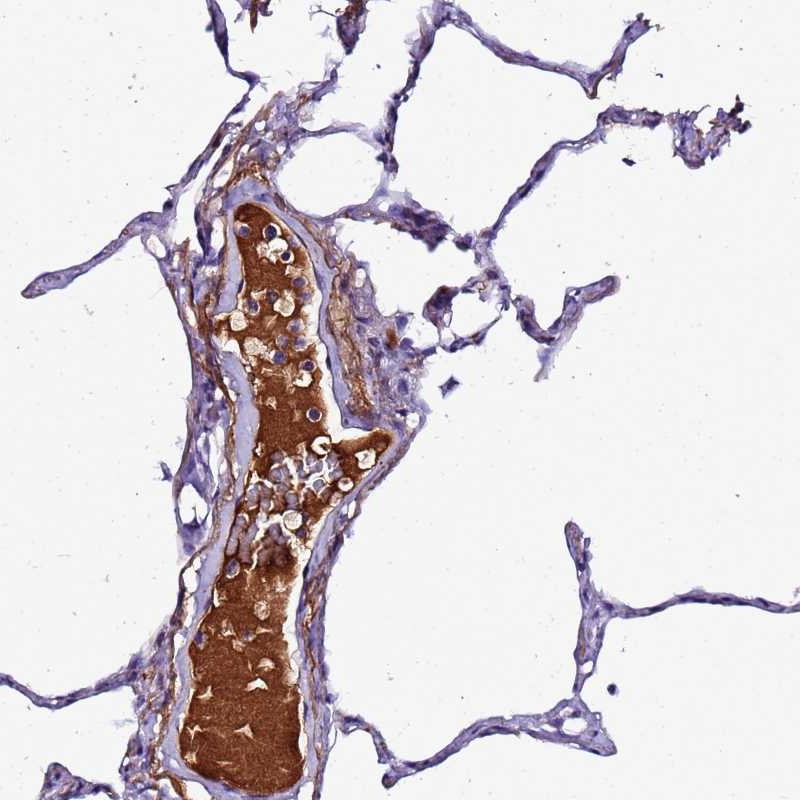

Immunohistochemical staining of human lung shows distinct positivity in plasma.